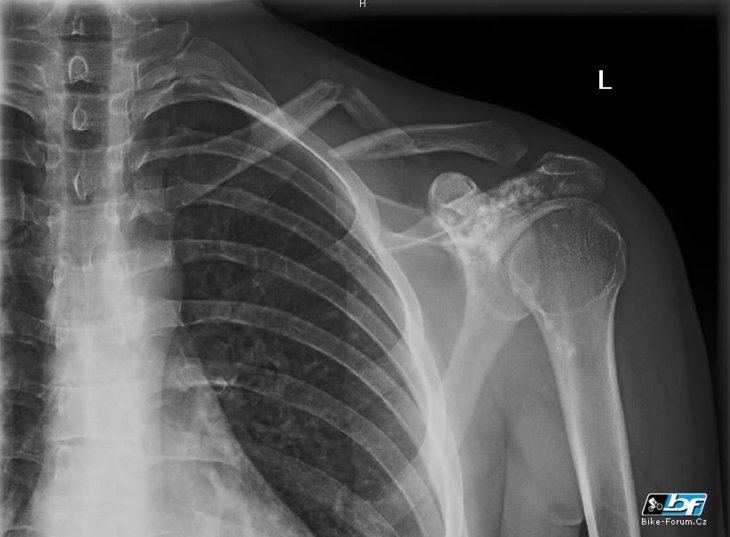

Jel jsem po lesní pěšině a podařilo se mi vlítnout předním kolem do strouhy vymleté vodou. Kolo ulítlo na pravou stranu a já na levou. Hlavou jsem udělal brázdu v jehličí a cestou asi něco přibral ramenem. No a klika byla na světě :)

Právě jsem na ten tvůj snímek taky koukal jak z jara…:) Taky si šel přes rodla na rameno?

Kurna, to je jak dejavu :) www.bike-forum.cz/…l-26068.html Jen mne to neoperovali, tak doufam, ze mi to za par mesicu nebudou s velkou slavou zase lamat, az zjisti, ze to neni funkcni :/